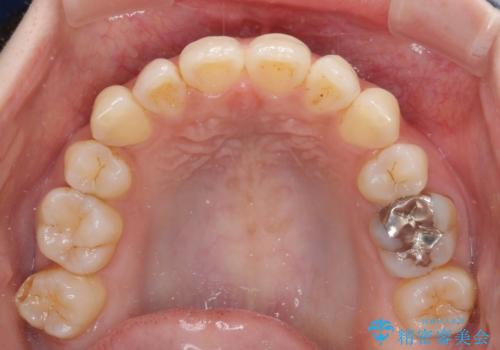

軽度な歯列不正 インビザライン・ライトによる矯正治療

- 上下前歯の叢生を気にして来院された患者様です。

費用を抑え、期間もあまりかけずに治療をしたいとのことで、インビザライン・ライトを用いて矯正治療を行うこととしました。

インビザライン・ライトは、製作できるアライナーの枚数に制限があるため、移動可能な量に限りがあります。

一方で、半年程度で治療を終えることができるため、軽度の歯列不正の患者様には大変お勧めです。